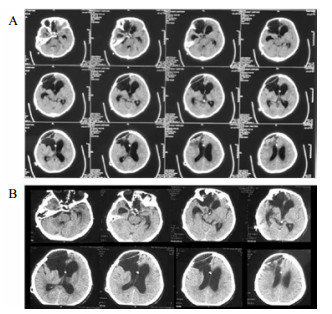

病例3,患者男,76岁,因“突发头痛昏迷,动脉瘤栓塞脑室引流术后半年余,脑积水分流术后3个月”入院。入院体查:GCS 7分,植物状态,双巴氏征阳性。V-P分流调压阀压力为1.0,脑积水虽已行分流术,但脑室仍明显扩大。拟诊:左前交通动脉瘤栓塞术后,脑积水V-P分流术后,持续性植物状态。脑室压力低于外耳道连线5 cm, 持续外引流脑脊液100~200 mL/d,同时去枕卧位,腹带加压包扎,适当增加补液量和扩脑血管改善脑微循环,力求增加颅内压和脑顺应性。脑室压力逐渐上升,然后调压至0.5,期间多次复查未见脑室大小明显缩小;但患者出现对威胁有眨眼反应,偶尔能对视觉对象定位,转为微小意识状态。发病4年后,即80周岁时,因为肺部感染而再次入院,控制肺部感染期间,考虑脑室仍扩大状态,予按压分流阀600次/d,患者意识显著上升,能主动要求饮食并表达喜好,能和家属互动做简单游戏。随访头颅CT见脑室较前有所缩小(图 5C)。

| A:第一次入院CT(脑出血栓塞和脑室外引流后);B:常规治疗后脑室扩大仍明显;C:2018年7月5日随访 图 5 病例3 CT |

病例4,男,26岁,因“车祸致颅脑损伤昏迷6个月”而入我院。急诊行开颅血肿清除术后1个月因脑积水而行V-P分流术。入院体检:GCS 7分,植物状态,四肢肌张力高,双巴氏征阳性。入院诊断为:重型颅脑损伤术后,脑积水V-P分流术后,持续性植物状态(图 6A)。考虑V-P分流过度引流,将分流调压阀调至最高的2.5水平,骨窗压力和头颅CT没有明显改变。遂将分流管皮下缝扎完全阻断,骨窗压力逐渐升高,术后复查CT(图 6B), 同时患者意识水平改善至微小意识状态。因脑积水加重再行V-P分流术,并择期予右额颞颅骨修补重建,随访头颅CT见图 6C。随后患者恢复至GCS 15分。

| A:男,26岁,颅脑损伤术后6个月入院时头颅CT;B:2015年1月4日分流管缝扎后CT;C:2017年3月8日V-P分流和颅骨修补术后 图 6 病例4 CT |